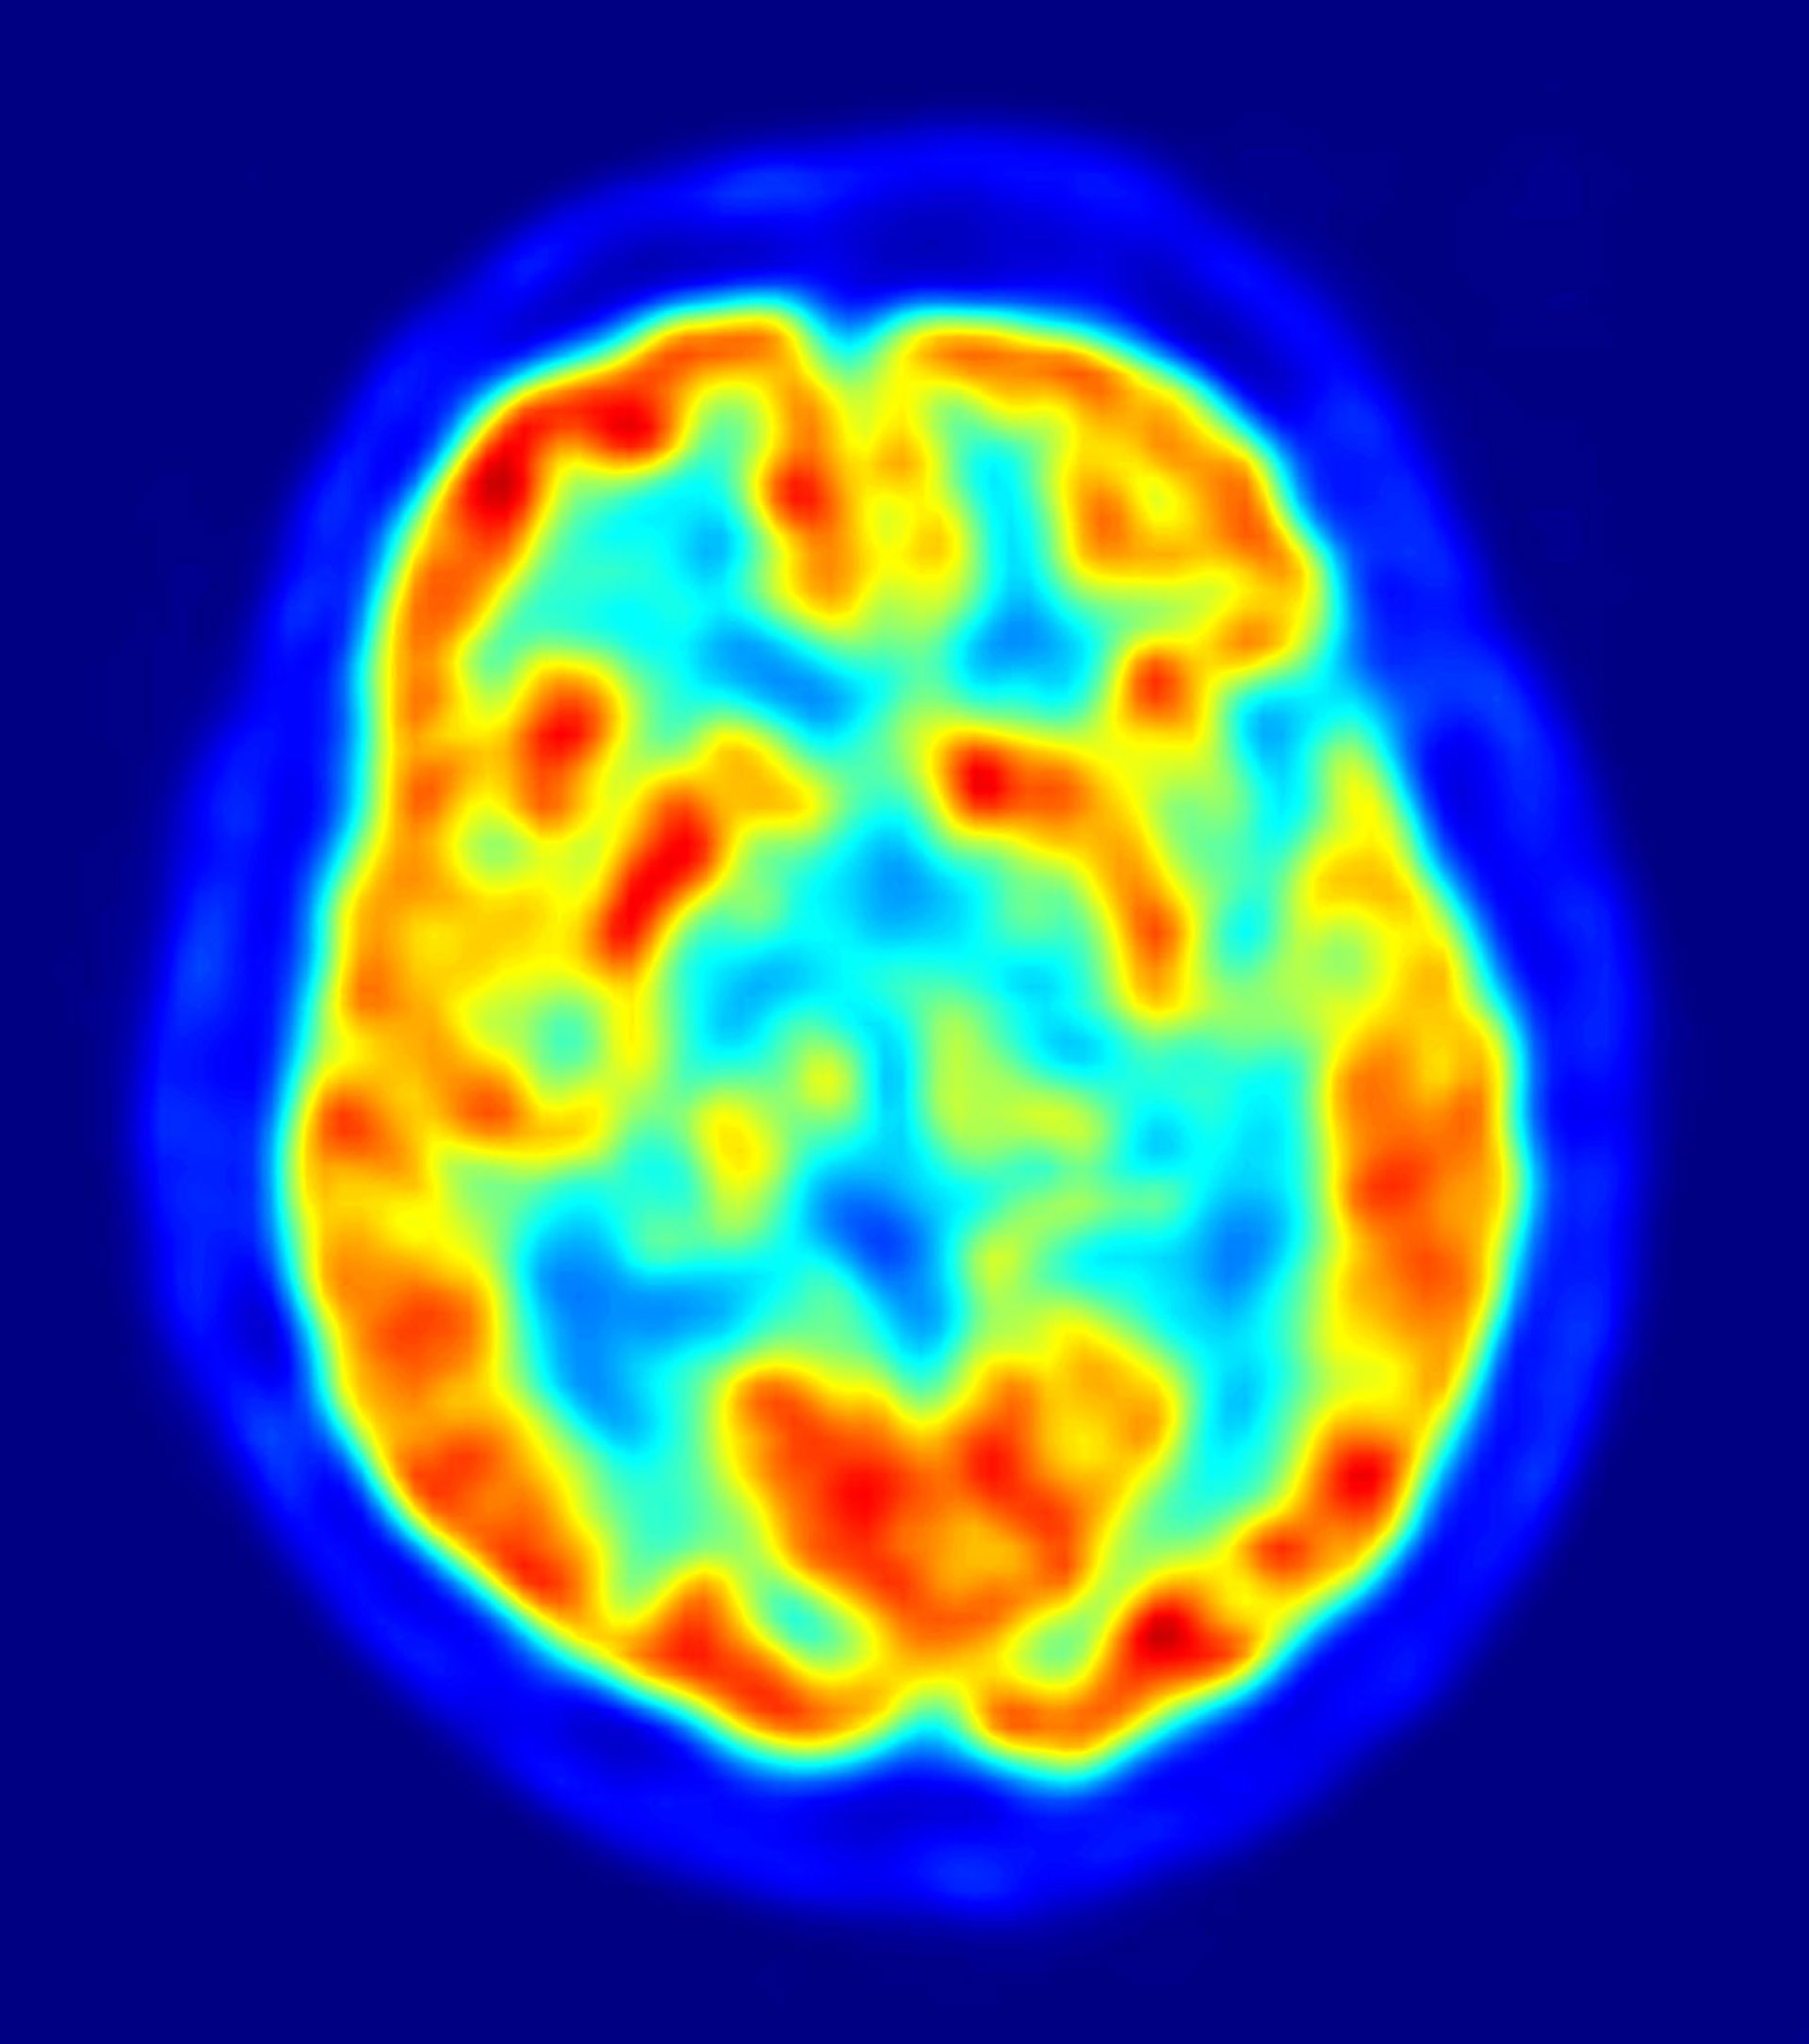

Los investigadores emplearon imágenes de resonancia magnética para comparar la respuesta neural a las recompensas de comida y económicas en adolescentes delgados con riesgo de obesidad en comparación con adolescentes delgados sin este riesgo. Los resultados sugieren que la vulnerabilidad inicial que da lugar a la obesidad podría elevarse en vez de mitigarse en el circuito de recompensa cerebral.

Los investigadores utilizaron imágenes cerebrales para examinar la extensión a la que el circuito de recompensa como el estriado dorsal se activaba en respuesta al consumo individual y anticipaba el consumo de los alimentos sabrosos como el batido de chocolate.

Los autores también emplearon otro paradigma para evaluar la activación cerebral en respuesta a recibir y a la recepción anticipada ante el dinero. La recompensa monetaria es un refuerzo general y ha sido utilizada frecuentemente para evaluar la sensibilidad a la recompensa. Los jóvenes con un alto riesgo mostraron una mayor activación en el circuito de recompensa al recibir tanto recompensa alimentaria como económica, así como una mayor activación en las regiones somatosensoriales en respuesta a recibir comida.